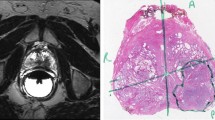

Voxel-wise comparisons have been largely used in the analysis of populations to identify biomarkers for pathologies, disease progression, or to predict a treatment outcome. On the basis of a good interindividual spatial alignment, 3D maps are produced, allowing to localise regions where significant differences between groups exist. However, these techniques have received some criticism as they rely on conditions wich are not always met. Firstly, the results may be affected by misregistrations; secondly, the statistics behind the models assumes normally distributed data; finally, because of the size of the images, some strategies must be used to control for the rate of false detection. In this paper, we propose a spatial (3D) nonparametric mixed-effects model for population analysis. It overcomes some of the issues of classical voxel-based approaches, namely robustness to false positive rates, misregistrations and large variances between groups. Examples on numerical phantoms and real clinical data illustrate the feasiblity of the approach. An example of application within the development of voxel-wise predictive models of rectal toxicity in prostate cancer radiotherapy is presented. Results demonstrate an improved sensitivity and reliability for group analysis compared with standard voxel-wise methods and open the way for potential applications in computational anatomy.

Ospina, J.D. et al. (2011). Spatial Nonparametric Mixed-Effects Model with Spatial-Varying Coefficients for Analysis of Populations. In: Suzuki, K., Wang, F., Shen, D., Yan, P. (eds) Machine Learning in Medical Imaging. MLMI 2011. Lecture Notes in Computer Science, vol 7009. Springer, Berlin, Heidelberg. https://doi.org/10.1007/978-3-642-24319-6_18